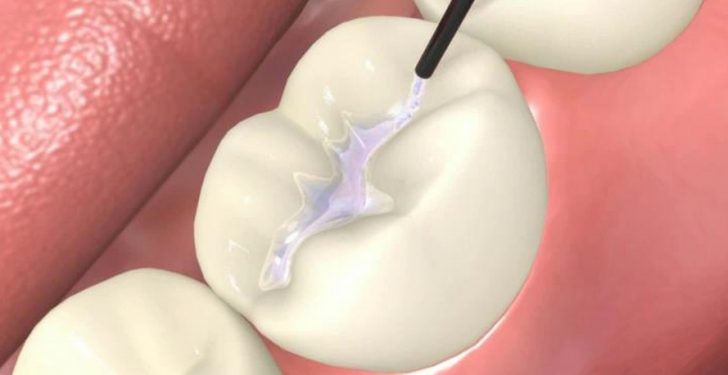

Restoratif Tedaviler (Diş Dolguları)

Dişin sert dokularında çürük, travma gibi çeşitli sebeplerle meydana gelen kayıpların kompozit ve amalgam dolgular, indirekt dolgu (İnley, Onley, Overlay) uygulamalarıyla tedavisi, ve yine sert fırçalama ve asidik beslenme gibi sebeplerle oluşabilecek dentin hassasiyetlerinin tedavisini kapsamaktadır.